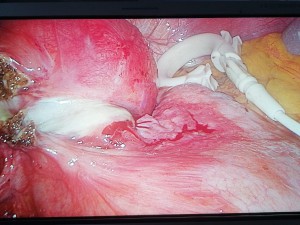

Durante la intervención se objetiva Banda gástrica deslizada con dilatación proximal del estómago sin signos de isquemia ni perforación.

Se realiza retirada de la banda gástrica por vía laparoscópica y el procedimiento transcurre sin incidencias por lo que la paciente es dada de alta al día siguiente de la intervención.